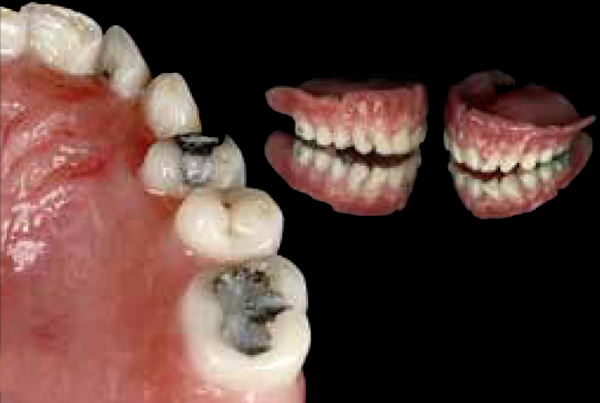

Fig 10. COCO Lux is used here for routine daily case documentation, providing light to the second molar region.

Figure 10